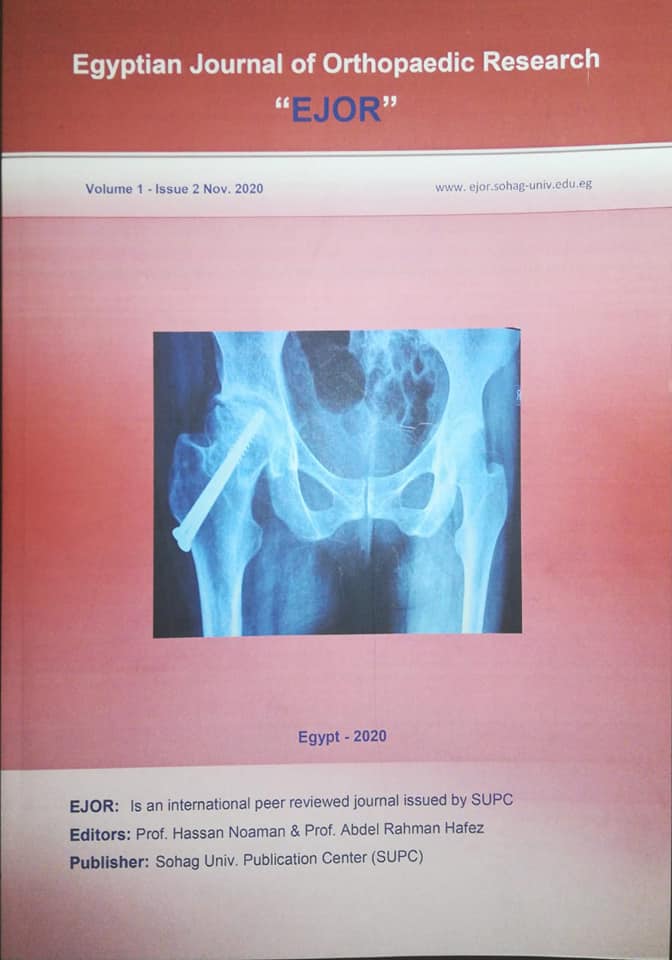

ومن جانبه أوضح الدكتور عبد الرحمن الشيخ رئيس قسم جراحة العظام، أن المجلة العلمية لجراحة العظام تصدر كل ٦ أشهر، وتم نشر ٤ أعداد منها اشتمل كل عدد على ١٠ أبحاث علمية تناقش كل ما هو جديد في مجال جراحة العظام والكسور والعمود الفقري، حيث يقوم بتقييم أبحاث المجلة عدد ٢٥ من المحكمين من الجامعات المصرية والاجنبية المختلفة مثل جامعات عين شمس، القاهرة، سوهاج، الاسكندرية، ايطاليا، المانيا، رومانيا، امريكا، بريطانيا، وغيرها .